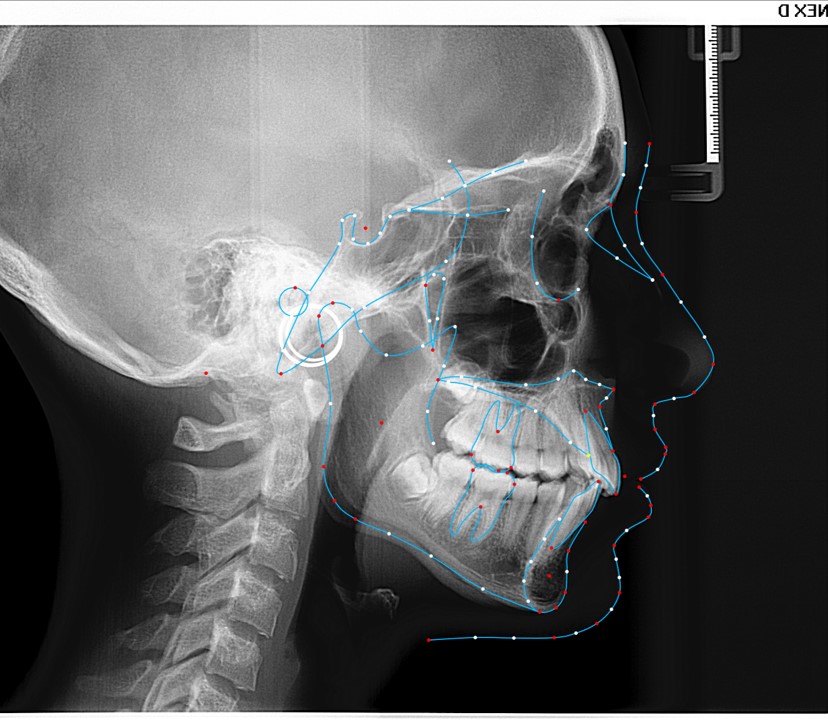

Chief complaint: We present the case of a 12-year-old female patient who came for an orthodontic evaluation, motivated by a family history of treatment. Clinical and radiographic analysis revealed a skeletal Class II malocclusion with molar and canine relationships also in Class II, moderate crowding in both arches, a deviation of the dental midline, and ectopic eruption of tooth 13. No functional issues with breathing or swallowing were observed, and oral health was generally good. A slight mandibular retrusion was noted in the soft tissue profile. A treatment plan was proposed using the Angel Aligner Pro system, aiming to correct dental misalignments and improve facial harmony through a minimally invasive, growth-adapted approach.

- Skeletal Class II

We approached the case by combining upper distalization using the A8 protocol with an asymmetric virtual jump. In this way, we solved the crowding without proinclining the incisors and improved the anteroposterior relationship through the use of elastics. In the lower arch, we carry out a development of the posterior sectors prior to the resolution of the crowding, in order to avoid roundtripping and excessive IPR of the incisors. To achieve an effective extrusion and distalization of 13, we combine the use of direct bonding button on vestibular of 13, with angelButton elastics mesial and distal to the canine. These mechanics help to ensure that the extrusion is real and that the aligner always remains adapted.

Treatment details

In the upper arch, the main goal will be to correct the Class II malocclusion by distalizing the upper posterior teeth in order to resolve crowding without proinclining the incisors. This movement will be accompanied by an asymmetric “bite jump” of 1 mm, which will help improve the skeletal Class II discrepancy, promoting mandibular projection, especially considering that the patient is still in the growth phase. Additionally, bilateral and symmetric expansion will be planned until a torque of 0° is achieved, allowing for proper transverse alignment and greater stability of the final result. Lingual button cutouts will be placed on teeth 14 and 24 to facilitate the required movements. To optimize control and retention, vertical mesial beveled attachments, as large as possible, will be placed on the premolars and molars, as well as on teeth 12 and 22, reinforcing the mechanics in the anterior sector. The inclination of the central incisors 11 and 21 will be corrected according to the visual reference provided in the clinical image. Furthermore, it will be necessary to center the upper midline by shifting it 0.5 mm to the left to achieve greater aesthetic symmetry. As for the lower arch, treatment will begin with a phase of expansion and derotation of the posterior teeth, which will set the stage for subsequent movements in the anterior sector. Once this goal is achieved, alignment of the teeth from canine to canine will proceed, aiming to minimize anterior interproximal reduction (IPR) and avoid unnecessary round- tripping movements of the incisors. Vestibular button cutouts will be made on teeth 36 and 46, while teeth 37 and 47 will have horizontal attachments that will serve as anchorage to ensure stability during treatment.